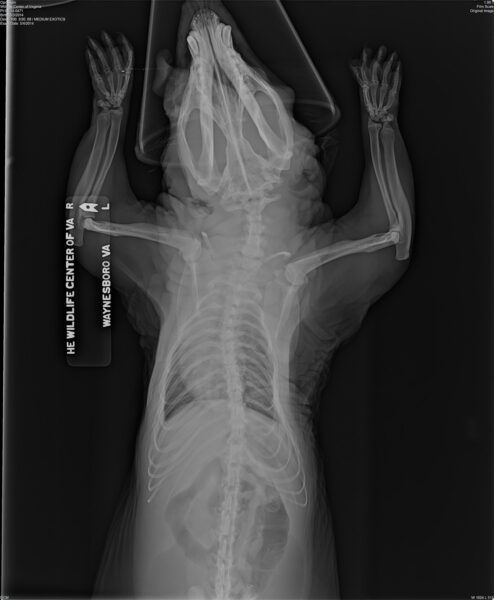

这张被圈养的负鼠的 X 光片显示了骨骼异常(腿部和脊柱弯曲),这种情况通常发生在圈养动物被未经训练的人喂食不适当的食物时。图片由弗吉尼亚野生动物中心提供